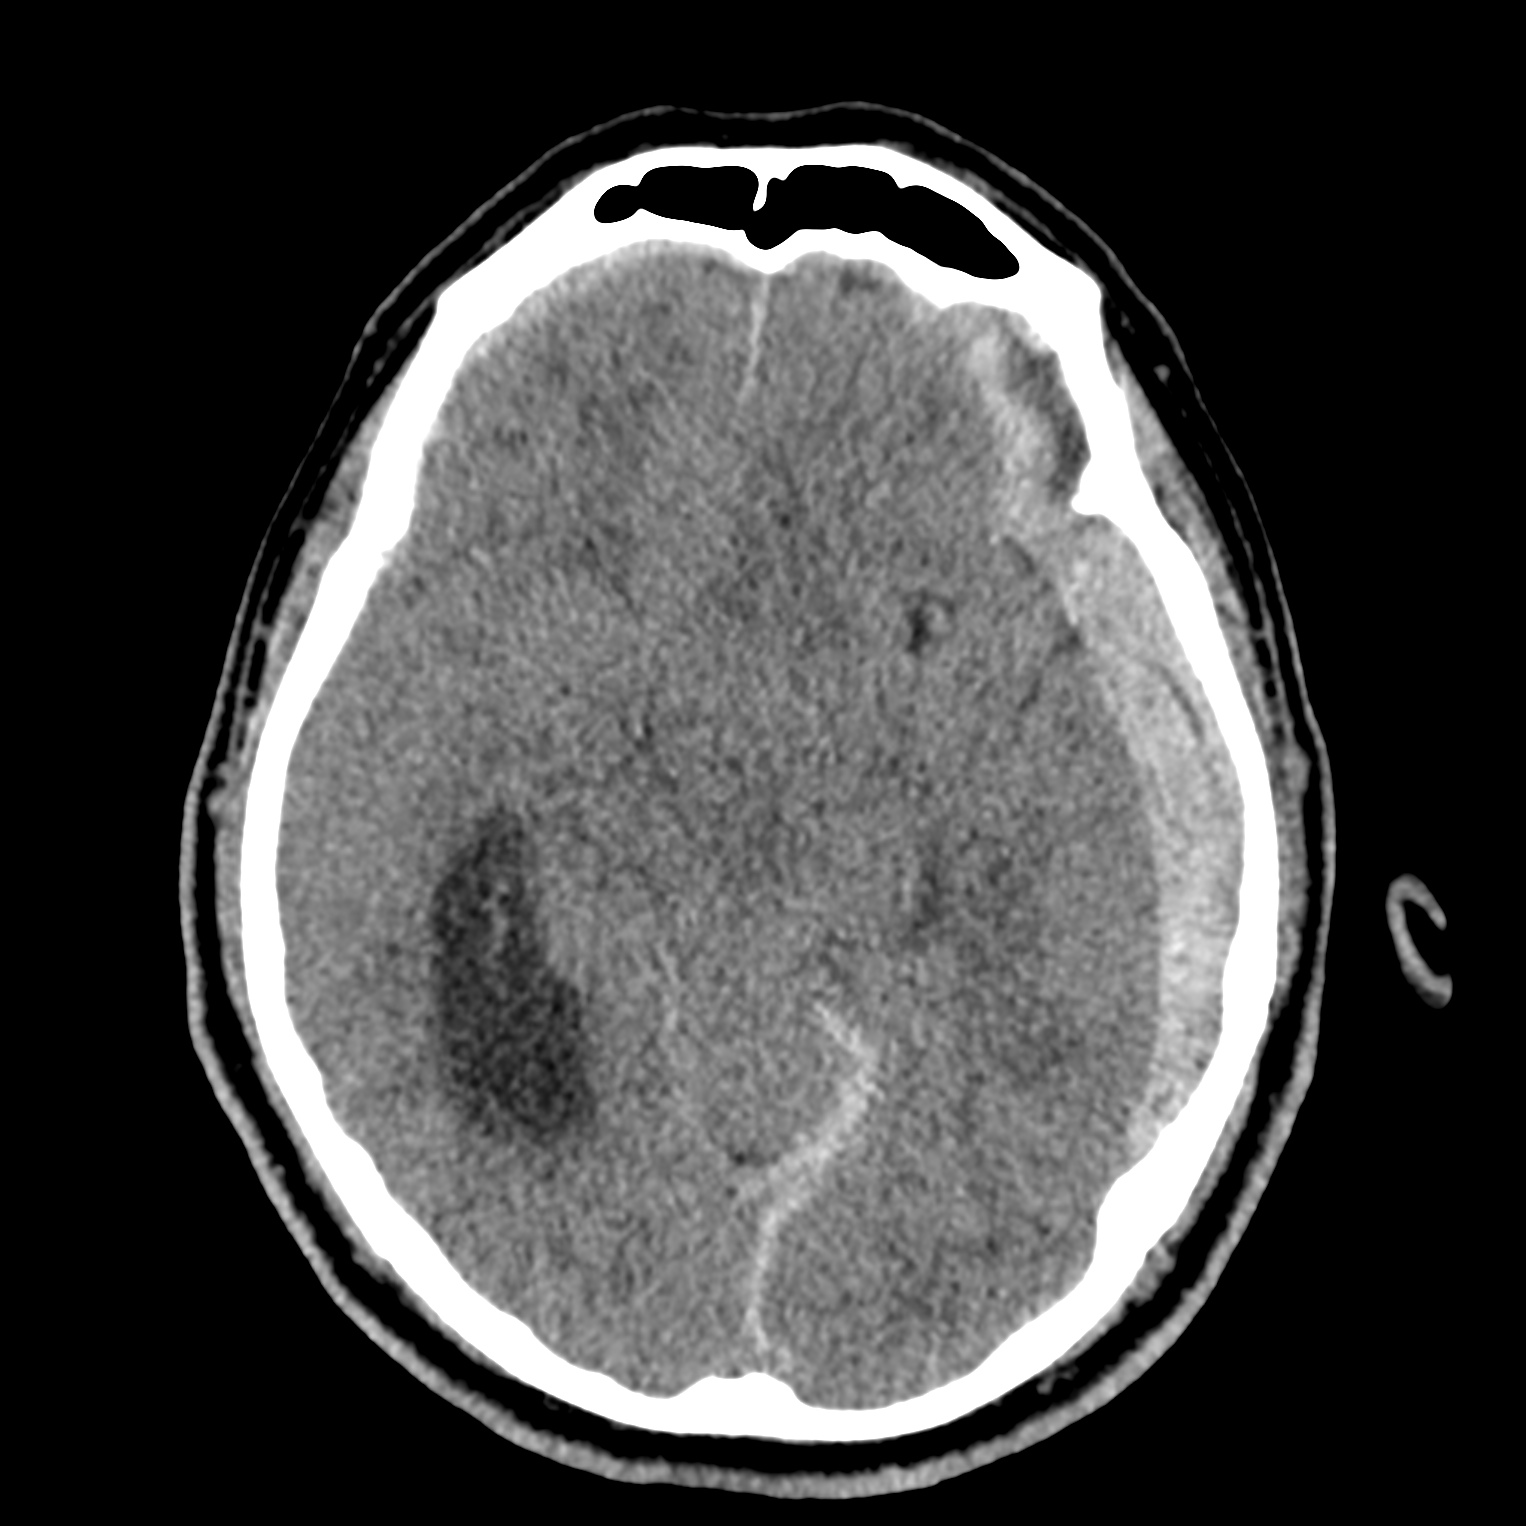

ちなみに画像診断とは、CTやMRIなどの画像を見て、正常か異常か、異常であればそれが何なのかを診断する仕事です。

Case courtesy of Andrew Dixon, Radiopaedia.org. From the case rID: 32383

医療従事者でなければ何のメリットも無いかもしれないのですが、実際の画像を自分でスクロールしながら学ぶことができるというのは、ものすごく大きなことだと思います。

さらに症例の解説を付け加えたら、読影能力アップのための強力なツールになるのではないかと期待しています。